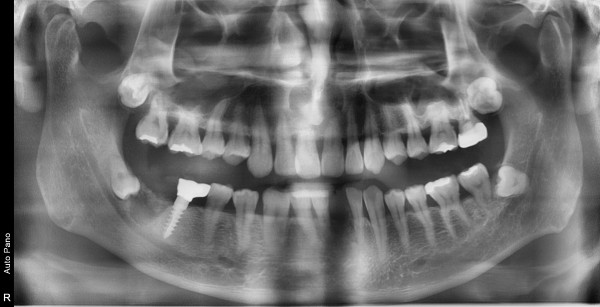

47세남자 우측구치부.하악전치부 뼈이식및임플란트식립